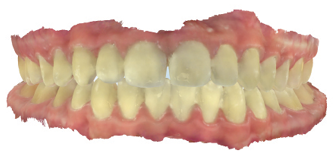

The majority of the orthodontic practices offer a period of “supervised retention” to their patients and communicates the customized retention recommendation with the patient’s general dentists. It is extremely important to work as a team to achieve long term clinical success in maintaining a functional bite and aesthetic smile. The general dentists continue to see their patients on a regular basis and have an opportunity to assess the orthodontic retainers and the bite after the supervised retention period is completed by the orthodontists. With great care, orthodontic retainers would serve for a long time (Fig. 1) without any major issues. However, in some cases, the failure to notice the clinical problems early on results in functional issues that would require a comprehensive orthodontic treatment to correct it (Fig. 2).

Fig. 2A

Fig. 2B

Fig. 2C